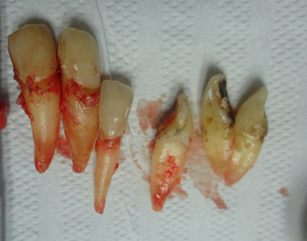

O final de uma periodontia inflamatória não tratada é este. A perda total dos dentes, todos íntegros, sem nenhuma cárie. Contudo, o biofilme por anos presente em suas superfícies, o tornaram para o Sistema Imunológico do paciente, um corpo extranho, ou seja um Antígeno.

Este (Ag), despertou todo o sistema imunológico do paciente, que iniciou a produção de anticorpos específicos (Ig), estimulando os osteoclastos a destruírem o osso alveolar, e iliminar o dente. Não foi o dentista que extraío estes dentes, mas o mecanismo de defesa do paciente os eliminou. Pois eles se tornaram um corpo extranho, que nesssecitava de ser eliminado, pois eles representavam um foco grave de inflamação, para o organismo do paciente.

Esta paciente veio ao consultório com a indicação de uma raspagem nesta região. Pois segundo seu Dentista, sua gengiva esta inflamada. Um exame radiográfico foi realizado, mostrando uma grande perda de osso, os dentes apresentavam uma grande mobilidade, com um prognóstico muito sóbrio. O caso da paciente, foi minuciosamente discutida com a paciente, mostrado que os dentes da bateria inferior anterior estavam perdidos, não haveria meios mais, de serem recuperados. Foi um choque no início para a paciente, contudo após um exame geral em sua boca, mostrando as profundas bolsas intraósseas, com inflamações generalizadas, e o risco que ela corria, não somente pela perda dos dentes, mas comprometimentos gerais incluindo problemas sérios cardíacos, ela se conscientizou da necessidade urgente de tratamento.

No início da profilaxia pré-cirúrgica, com as pontas de ultrassom, podemos demonstrar a paciente a necessidade do procedimento indicado. Os dentes praticamente seriam removidos apenas com uma profilaxia rigorosa. Em certos casos, e dependendo dos pacientes, é importante mostrar as alterações patológicas, assim como documentar os procedimentos, que forem realizados. Os dentes foram extraídos, pois, estavam condenados. Apaciente não usava, pois estavam moles e doíam.

Todos dentes condenados tiveram que ser extraídos. As remoções foram feitas com muita cautela para não haver rompimento da crista óssea, assim como do septo interdental. Esse procedimento deve ser realizado em todas exodontias, para preservar o máximo de tecido ósseo alveolar.